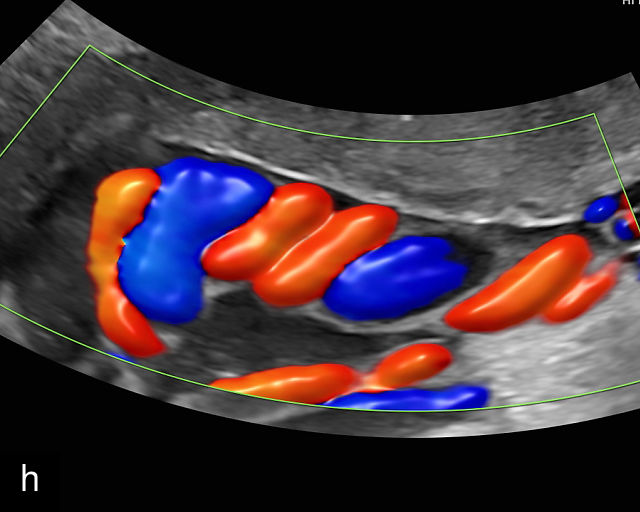

Abnormal cord coiling

The umbilical cord coiling index (UCI) is defined as the number of complete vascular coils per cm of cord, with a normal UCI averaging around 0.2.185,191 A hypocoiled cord is typically defined as having an UCI of less than 0.2, or below the 10th percentile, with approximately one coil per 10 cm of cord (Figure 18a–c). In contrast, a hypercoiled cord has an UCI greater than 0.3, or above the 90th percentile (Figure 18d; Video 9). It is estimated that hypocoiling of the cord occurs in between 4% and 15% of pregnancies.185,191

18

Umbilical cord hypocoiling and hypercoiling. (a) Grayscale ultrasound image of hypocoiled cord. (b) Color flow Doppler image of hypocoiled cord. (c) Grayscale and color flow Doppler image of hypocoiled cord. (d) Grayscale image of hypercoiled cord.

9

Imaging of umbilical cord hypercoiling using grayscale (a–c) and color Doppler (b) ultrasound.

Several factors influence cord coiling, including cord length and fetal movement.191,208 Coiling tends to increase with gestational age and serves as a protective mechanism, shielding the fetal vessels from compression. Excessive coiling may obstruct blood flow, while hypocoiling may increase the risk of vessel compression and adverse perinatal outcome.209 Hypocoiling has also been associated with conditions characterized by reduced fetal movement.

While sonographic assessment of cord coiling is feasible, the sensitivity and specificity of this finding in isolation are limited. As a result, there are no current recommendations for routine evaluation of the UCI during obstetric ultrasound. This limitation is further compounded by the fact that most UCI reference values have been derived from postnatal examination of the cord rather than by prenatal imaging. Most adverse outcomes associated with abnormal umbilical cord coiling have been reported based on pathological examination of the placenta and cord following stillbirths or other adverse events, rather than on the prenatal ultrasound detection of abnormal cord coiling.6

Nonetheless, efforts have been made to assess coiling prenatally.208 Predanic et al. reported a correlation between second-trimester ultrasound measurements of cord coiling and findings at birth but noted that prenatal ultrasound was less accurate in identifying hypocoiled or hypercoiled patterns.188,210,211 In contrast, Ma’ayeh and colleagues, in a prospective study of 72 patients, found that second-trimester sonographic assessment of the UCI did not reliably predict coiling at birth or correlate with perinatal outcomes.212 Therefore, routine assessment of umbilical cord coiling is not recommended. However, if a cord appears markedly hypocoiled or hypercoiled during a standard ultrasound examination, closer surveillance with serial ultrasounds should be considered.